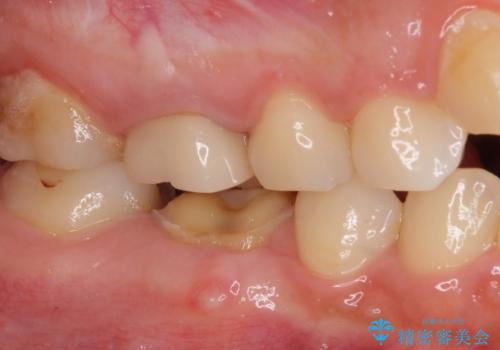

- 奥歯のクラウンが外れたままにしているとのことで来院された患者様です。

奥歯に特に症状はなかったのですが、排膿路が歯肉に認められたため、根管治療を行った上でオールセラミッククラウンにて補綴治療を行うこととしました。